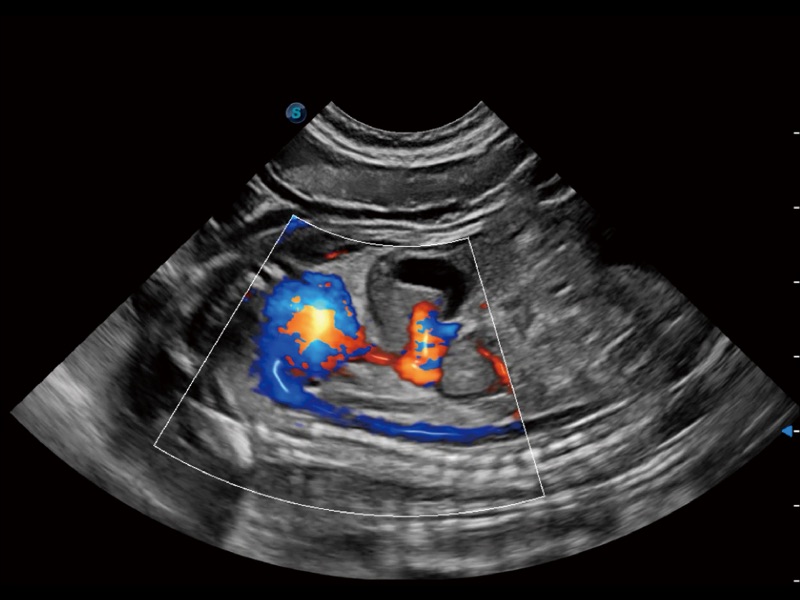

通过创新的 Matrix E自适应滤波器和超长时间域算法,极大提升超低速微细血流的检出能力,同时更精准地滤除软组织和噪声信号,为兽用医生提供以往无法通过常规血流获得的疾病诊断信息。

通过色彩血流和实时宽景相结合,可观察到完整的静脉或动脉的血流,方便医生检查。实时扫查过程中,如有任何操作失误也可以很容易地进行回扫擦除,而不会中断扫查。

ProPet 70 全新的动物超声智能软件和丰富的探头群,为动物医生提供了高清晰度和精细分辨率的图像,无论在宠物、马科、畜牧还是实验室动物等应用中都可以轻松应对,为您的日常工作带来满意的体验。